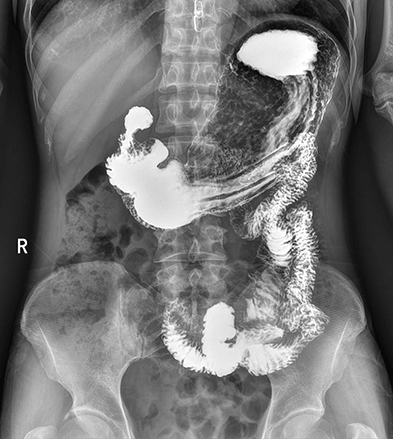

临床图像